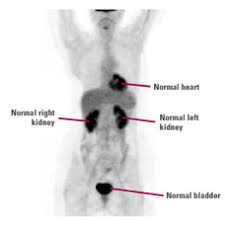

With cancer cells, they appear as bright spots due to its higher metabolic rate compared to normal cells. It is common for patients to receive a diagnosis for cancer of unknown primary. With that being said, not all cancers can be detected by pet. This substance is often called a tracer, because it helps reveal cancer in the body. Each has its own strengths.

For cancer, pet is especially useful as it can scan the entire body and pinpoint both a primary tumor and areas of metastasis (where the cancer has spread).

The test has only a limited ability to detect small tumors. Pet scan for breast cancer a positron emission tomography (pet) scan is an imaging test that uses a radioactive substance (called a tracer) to look for potential spread of breast cancer. In some instances, cancers may not show on the scan. Combining a pet scan with an mri or ct scan can help make the images easier to interpret. Pet scans can be used to determine how much cancer is in a person's body and how far the cancer has spread, which is called staging. This tracer can help identify areas of cancer that an mri or ct scan may miss. With cancer cells, they appear as bright spots due to its higher metabolic rate compared to normal cells. However, the pet scan uncovers every unusual activity in the body and is more sensitive than any other existing imaging test. Pet/ct scan can accurately localize lymph node metastasis and help to monitor the response to chemotherapy. Breast positron emission tomography (pet) scan is an imaging test that uses a tracer (radioactive substance) to look for symptoms of breast cancer. Pet scans can also help to assess whether metastatic breast cancer is responding to the treatment. Pet scans are not used to screen women for breast cancer. Pet/ct scans using axumin tracer, approved by fda last year and newly approved by medicare in some areas, are starting to be done at different locations.